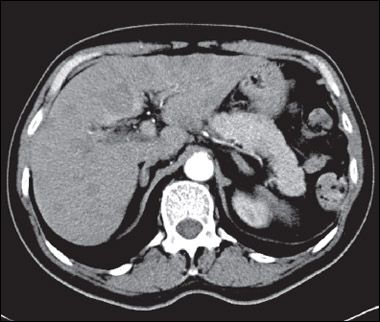

A CT scan of the chest showed an amorphous soft tissue mass that encased and constricted the right main pulmonary artery and the right main stem bronchus (A). Extensive round masses were visible in the liver; the largest mass was in the right medial hepatic lobe and measured 2.7 × 2.4 cm (B).

SCLC typically presents as a large central mass (as in this patient) with mediastinal adenopathy. SCLC can infiltrate the submucosa, causing either intrinsic or extrinsic compression of the bronchi. SCLC has a propensity for spreading to the liver, brain, bone, and bone marrow. The neutropenia and thrombocytopenia seen in this man can be explained by the infiltration of his bone marrow by the SCLC. In a series of 129 patients with SCLC, 30% had bone marrow involvement. However, in only 2.3% was the bone marrow the only site of metastatic disease.7 Other presenting symptoms include cough, dyspnea, hemoptysis, chest pain, postobstructive pneumonia, and the paraneoplastic syndromes mentioned above.